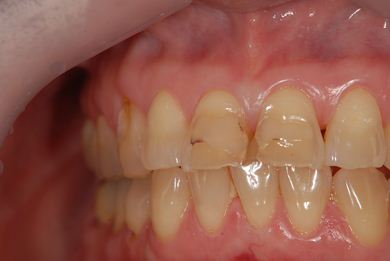

治療後

• 治療後